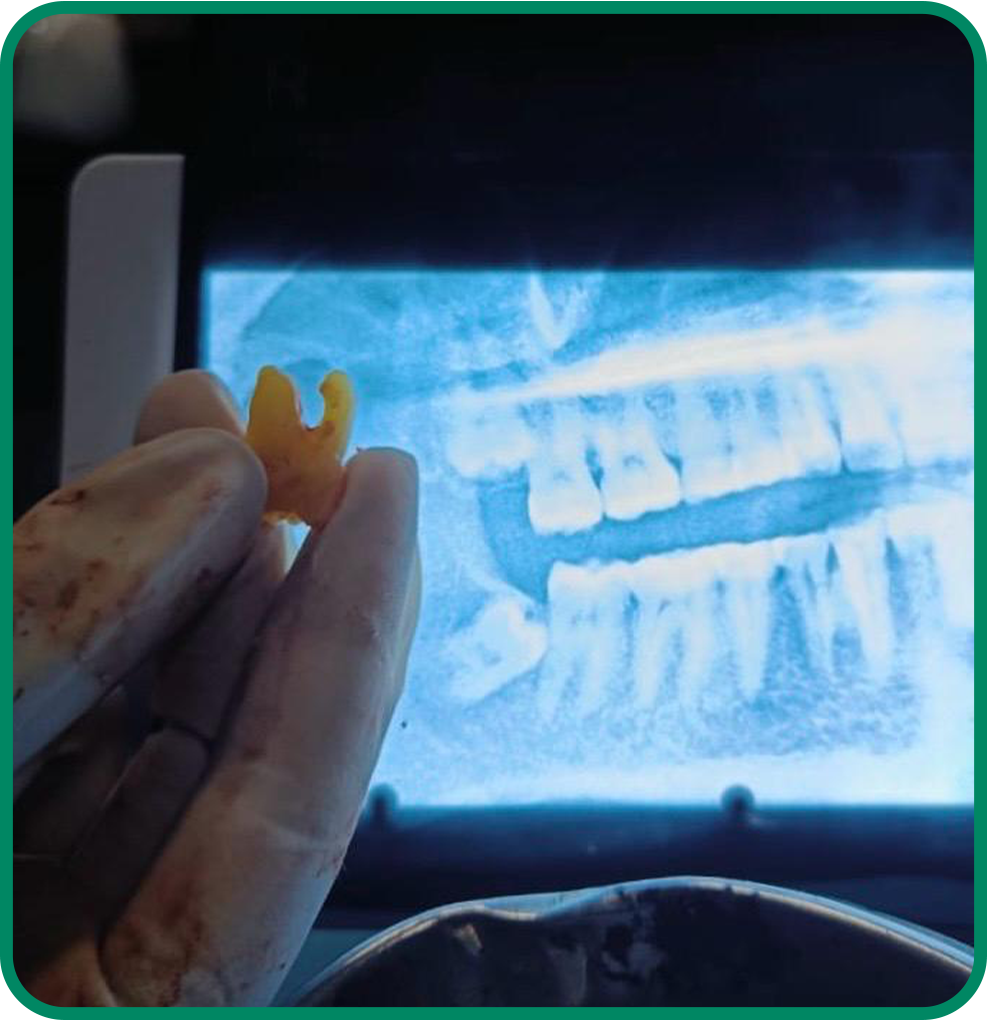

Wisdom Teeth Extraction

Safe and gentle removal of impacted wisdom teeth to prevent pain, infection, and future dental complications.